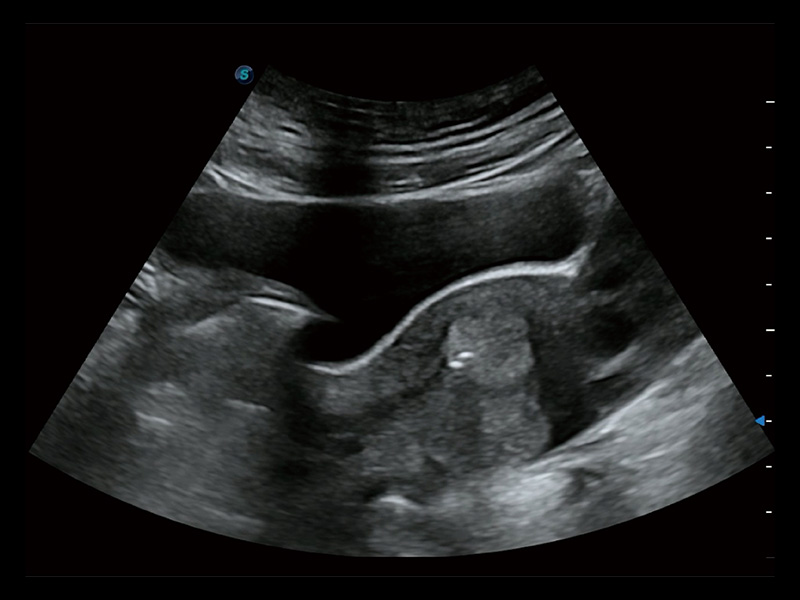

“生育问题”即关系民族复兴,也关系亿万家庭的幸福。随着婚育年龄推迟、社会压力增加等因素,越来越多人群也面临着“生不出、生不好”的问题。辅助生殖作为治疗不孕不育最有效的方法之一,也逐渐成为育儿新希望。而超声检查能为生殖需求人群的初诊评估提供宝贵的信息。 P20 Elite是开立医疗匠心打造的一款生殖应用型彩超。她继承开立医疗高端极光平台,突破性地将多款新型芯片及硬件模块进行整合,均衡了高端系统性能与小巧灵动机身。P20 Elite卓越的图像质量搭载专科探头,旨在为您提供全面的辅助生殖解决方案。

P20 Elite配备了丰富的生殖探头群和临床应用功能,在卵泡监测、穿刺取卵、胚胎移植、妊娠确认等领域,为生殖需求人群提供了新的临床机会,重新定义高端超声如何应用于生殖健康检查。

通过线上云会诊平台,实现县级医院与上级医院患者卵泡数据互联互通。避免重复性卵泡测量,提高诊断效率。